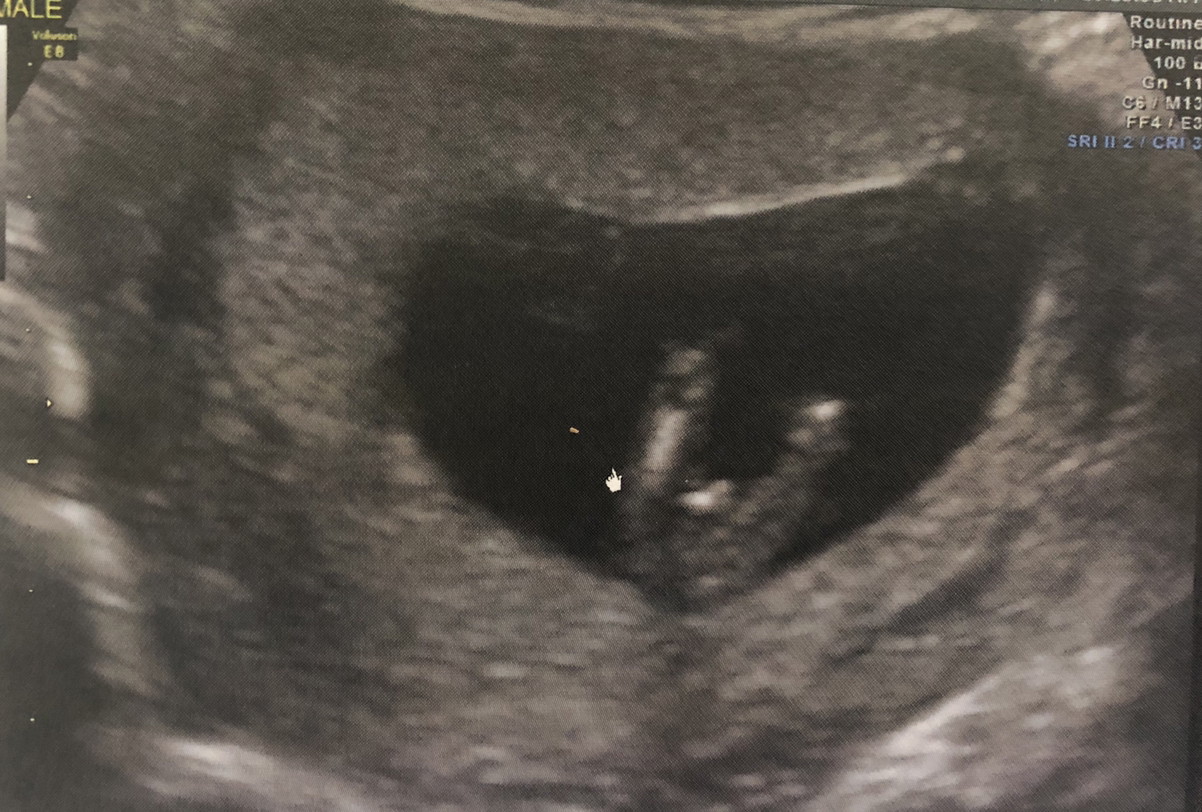

ผญ.จ้า

ผญ.ค่ะ

ผญค้า

ญ ค่ะ